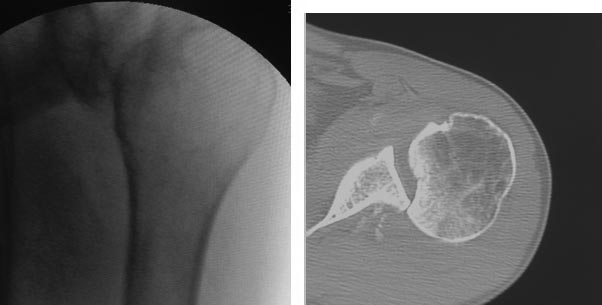

Мужчина около 40 лет. Задний вывих плеча. На момент госпитализации 2 месяца. Труд физический. Лечился амбулаторно с "ушибом".

Варианты оперативно лечения-1 вправление вывиха и фиксация спицами. 2 Вправление вывиха и деротационная остеотомия плеча 3. Вправление вывиха и костная пластика 4. Вправление вывиха с транспозицией подлопаточной мышцы в зону костной импрессии.

На томограмме вроде вывиха нет. Хилл-Сакс есть. Это уже после вправления?

А вот в этом и заключается коварство задних вывихов. Они ротационные. И, часто, пропускаются. Данный пациент жаловался, по прошествии времени, на полное отсутсвие наружной ротации и ограничение отведения до 70 градусов. ( рука поднималась за счёт лопатки). Интраопеоационные и послеоперационные снимки выложу в презентации. Пока её формирую. Просто времени мало, а работы..... очень много. Мнения интересны. Ведь не каждому « так везёт»